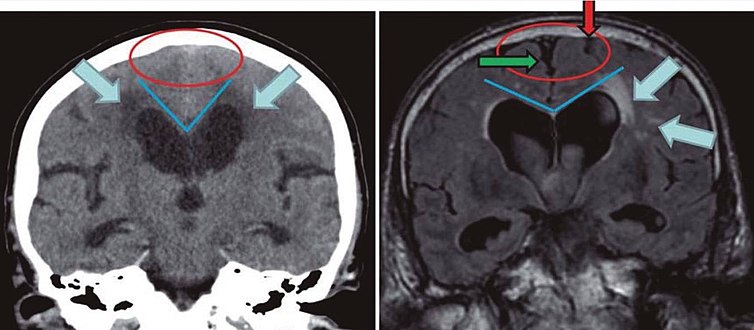

Imaging findings normal pressure hydrocephalus versus brain atrophy.[9]

Normal pressure hydrocephalus Brain atrophy

Preferable projection Coronal plane at the level of the posterior commissure of the brain.

Modality in this example CT MRI

CSF spaces over the convexity near the vertex (red ellipse ) Narrowed convexity ("tight convexity") as well as medial cisterns Widened vertex (red arrow) and medial cisterns (green arrow)

Callosal angle (blue V) Acute angle Obtuse angle

Most likely cause of leucoaraiosis (periventricular signal alterations, blue arrows ) Transependymal cerebrospinal fluid diapedesis Vascular encephalopathy, in this case suggested by unilateral occurrence

MRI scans are preferred. The distinction between normal and enlarged ventricular size by cerebral atrophy is difficult to ascertain. Up to 80% of cases are unrecognized and untreated due to difficulty of diagnosis.[10] Imaging should also reveal the absence of any cerebral mass lesions or any signs of obstructions. Although all people with NPH have enlarged ventricles, not all elderly with enlarged ventricles have primary NPH. Cerebral atrophy can cause enlarged ventricles, as well, and is referred to as hydrocephalus ex vacuo.